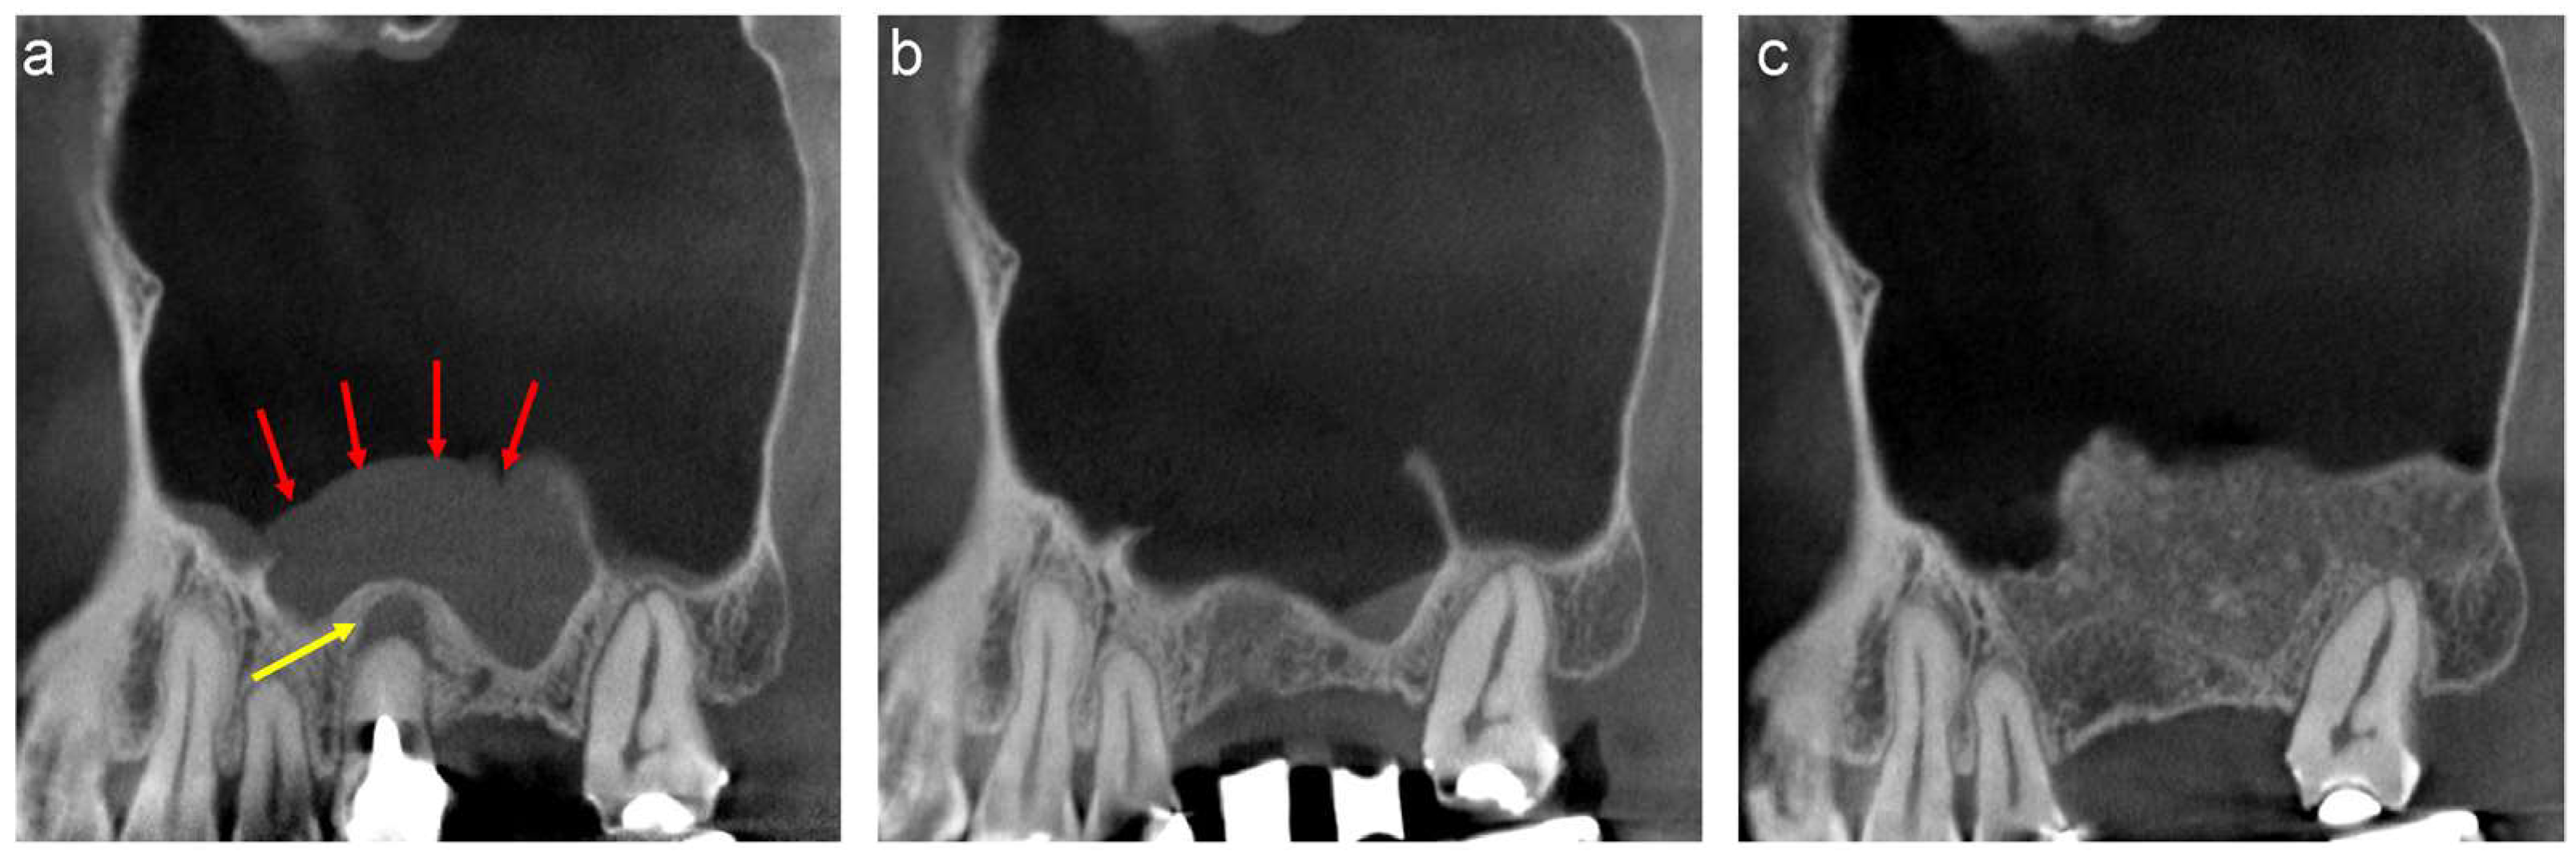

Preliminary suction of the contents was performed with a fine 18-gauge needle in cases with large APs (>15 mm) to reduce the volume to facilitate the clamping of the AP (Figure 5a,b). The surface of the AP was clamped with forceps and herniated through the bony window with gentle outwards traction without preserving the integrity of the periosteum underneath the AP (Figure 5c,d). The base of the AP, which appears as a sessile dome-shaped, well-defined, faintly radiopaque lesion, is usually present on the floor of the sinus cavity. In contrast, the AP appears as a round when the base of the AP is present at the lateral wall of the maxillary sinus (Figure 3a,b). The position of the base must be evaluated preoperatively as the AP, including the base, should be enucleated together.

Figure 5.

(a) Mesiodistal section of the CT images acquired at the first visit. A large, well-defined, and faint radiopaque lesion can be observed in the maxillary sinus. (b) Preliminary suction of the lesion contents was performed using a fine 18-gauge needle. (c) Endoscopic view of the antral pseudocyst (AP) after suction of the contents. The AP has reduced in size compared to that observed on the CT images during the preliminary section. (d) The surface of the AP was clamped with forceps and herniated through the bony window with gentle outwards traction. (e) Endoscopic view of the enucleated area. A contentious haemorrhage was observed at the base of the AP. (f) Oxidised regenerated cellulose was applied to stop bleeding. (g) The bony window is covered with a resorbable collagen membrane to reduce blood flow into the sinus cavity. (h) The AP was enucleated as a lump with a base. (i) Histological specimen of the enucleated AP (haematoxylin and eosin staining). The outer surface of the lesion was lined with ciliated columnar epithelium and the inner surface was lined with fibrous connective tissue without epithelium. (j) Mesiodistal section of the CT image obtained after enucleation. A flat, faintly radiopaque area can be observed, demonstrating an accumulation of physiological saline or blood at the bottom of the maxillary sinus (red arrows). (k) Swelling of the sinus membrane increased one-week following enucleation (yellow arrows). (l) Swelling of the sinus membrane decreased three months after enucleation. (m) Volume-rendering image obtained three months after enucleation. The bone defect persists in the bony window. (n) Dissection of the scar tissue between the sinus membrane and oral mucosa was necessary at the bone defect area to avoid perforation of the sinus cavity. (o) Scar tissue was observed in the bone defect area without perforation after the elevation of the mucoperiosteal flap. (p) β-TCP granules fill the space between the elevated periosteum and the exposed bone surface of the maxillary sinus. (q) The bony window was tightly covered with a titanium mesh plate and three titanium microscrews. (r) Mesiodistal section of the CT image obtained after sinus floor elevation. Sufficient radiopaque granules can be observed in the augmented area.

The use of an endoscope is not mandatory; however, it aids in confirming the enucleation of APs and haemostasis through the small bony window. Haemostasis was performed using oxidised regenerated cellulose in cases with continuous haemorrhage (Figure 5e,f). The bony window was covered with a resorbable collagen membrane to reduce blood flow into the sinus cavity, and the mucoperiosteal flap was closed (Figure 5g).

4.4. Lateral Approach after Enucleation

Swelling of the sinus membrane is observed due to traumatic stimulation one week post-surgery (Figure 5j,k), which diminishes three months later (Figure 5l). The ciliated columnar epithelium cells at the base of the AP are removed during the enucleation, and the periosteum underneath the AP is exposed. Hence, the decrease in the swelling of the sinus membrane indicates the regeneration of the columnar epithelial cells and restoration of the ciliary motility. Thus, sinus floor elevation can be performed four months following enucleation of APs.

Bone defects in the bony window persist for four months following the enucleation of APs (Figure 5m). Therefore, dissection of the scar tissues between the sinus membrane and oral mucosa must be performed in the area with the bone defect during the elevation of the mucoperiosteal flap for sinus floor elevation using the lateral approach (Figure 5n,o). The periosteum underneath the sinus membrane is elevated after enlarging the bony window, and the β-TCP granules are filled in the space between the elevated periosteum and the exposed bone surface of the maxillary sinus (Figure 5p). The bony window is covered tightly with a titanium mesh plate and three titanium micro screws to avoid the migration of the β-TCP granules due to the postoperative sealing of the sinus membrane (Figure 5q,r) [5].